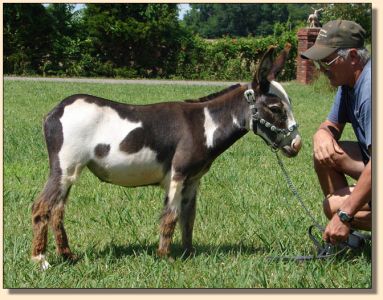

- 9/24/07 @ 9:30pm! Bow's baby was breech and she was in labor for nearly two hours before

the vet arrived and delivered the baby alive! A true miracle...she is a gorgeous, tiny,

dark spot but she needs your prayers. She was born without a tail or anus. We are taking

her to UT Vet Hospital in the morning. This baby wants to live. The vet was amazed

that she was still alive and we were too. Bow is doing fine and loves her baby who she thinks

is just perfect. A big thank you to our wonderful vet, Dr. Greg Harris!!!!

Update

9/25/07 @ 10pm - Bow and Pony-Tailed Lass are at UT Vet Hospital in Knoxville. The prognosis

is good. Her anus is going to be able to be repaired with an operation but they hear a slight

heart murmur. Her heart will be evaluated further tomorrow to see if she is strong enough

for the operation on Thursday. Stay tuned for updates and keep those prayers coming!

Update - 9/28/07: Bow and Lass are home. They will be returning in three weeks for

the surgery. The vets wanted her newborn skin to be more mature before they operate. You

can see them on our live streaming barn

cam now!

Update - 11/02/07: The vet hospital in Knoxville just called us and

scheduled Pony-Tail's surgery for November 6th. The vet that is doing the surgery is Dr.

Blackford. The retired vet that is an expert in this kind of surgery that is coming in to

assist in the surgery is Dr. Krahwinkle. Everyone say a prayer for Pony-Tail. I am sure

she is going to come out of the surgery with flying colors!

Pony-Tailed Lass Update

- 11/09/07 @ 10:34am: PTL is out of surgery!! She is up and nursing. She will stay at UTK

until Tuesday for observation and is expected to be able to come home on Tuesday! The vet

that did the surgery is Dr. Blackford. The retired vet that is an expert in this kind of

surgery that advised Dr Blackford about the surgery was Dr. Krahwinkle.

Update

11/13/07 @ 8am: Pony-Tailed Lass has gone back in for surgery this morning. They are going

to remove a piece of tissue between where her colon stopped and the new hole the surgeon

made on her first operation. This may cause scar tissue to completely block her passage

but as it is now the tissue is making the opening too small for her to poop normally. If

scar tissue forms they will do a third operation and put her back basically the way she

was. Please keep Pony-Tail in your prayers!

11/19/07: Pony-Tail is home from her

operation and so far it is a complete success!

Update 12/09/07: Pony-Tail is continuing

to do well. She is going for her check up next week when we schedule her visit back to the

vet school in Knoxville. You can see her on our barn cam occasionally as she has free access

to all four cams now.

12/12/07: Pony-Tail's check-up at the University of Tennessee

Vet School today was a good one.

1/02/08: Pony-Tail's final checkup at the University

of Tennessee Vet School was today and she received a clean bill of health and was pronounced

well. She does not have to go back to the vets unless complications arise later down the

road!